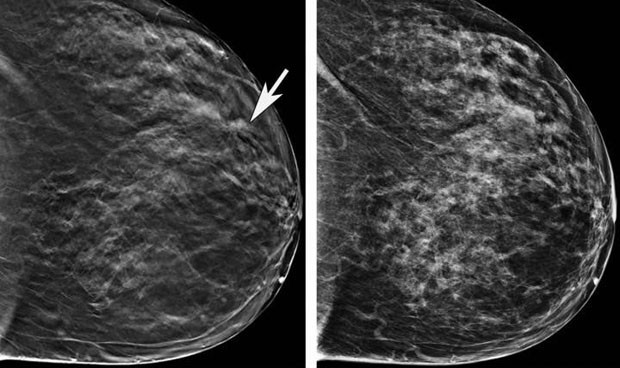

La mamografía es el el principal método de cribado de cáncer de mama.

La mamografía es el método que se suele utilizar para detectar el cáncer de mama, si bien el diagnóstico de este tumor sigue siendo un "desafío" para los profesionales dado que es "difícil" leer estas imágenes de rayos X  y, a menudo, se producen falsos positivos y negativos.

En concreto, para evaluar su eficacia, los expertos, cuyo trabajo ha sido publicado en la revista Nature, analizaron datos de mamografías de más de 76.000 mujeres del Reino Unido y más de 15.000 mujeres de Estados Unidos, con el fin de comprobar si el sistema podía aprender a detectar signos de cáncer de mama en los escáneres.

Posteriormente, evaluó a más de 25.000 mujeres del Reino Unido y 3.000 de Estados Unidos, lo que permitió a los investigadores comprobar que en este análisis se habían reducido un 5,7 por ciento los falsos positivos entre las mujeres estadounidenses y un 1,2 por ciento entre las inglesas. Además, los expertos observaron una disminución del 9,4 por ciento de los falsos negativos en Estados Unidos y del 2,7 por ciento en Reino Unido.

En este punto, los investigadores han informado de que el modelo de inteligencia artificial necesita menos información para identificar el cáncer de mama que los radiólogos, quienes se basan en las historias clínicas de los pacientes y en los resultados obtenidos en mamografías anteriores.

"A pesar de trabajar sólo con las imágenes de rayos X más recientes, nuestro modelo ha superado a los radiólogos en la identificación precisa del cáncer de mama", han recalcado los expertos de Google, tras informar de que hay algunas señales "prometedoras" de que el modelo podría aumentar la precisión y eficiencia de los programas de detección del cáncer de mama, así como reducir los tiempos de espera y el estrés para los pacientes.